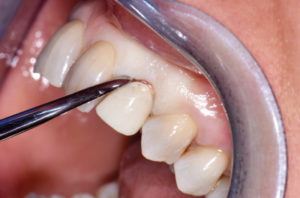

Durante i 5 mesi di guarigione, la paziente porta una protesi parziale mobile; a guarigione del sito post-estrattivo si evidenzia una buona conservazione dei volumi osseo-gengivali, se pur presente una recessione distale all’elemento 21 (Figg. 26-30).

- Fig. 26

- Fig. 27

- Fig. 28

- Fig. 29

- Fig. 30